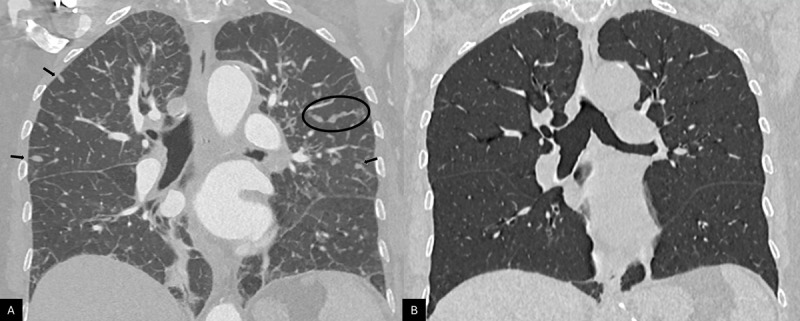

Teaching point: Transient interlobular septal nodules displaying a characteristic branched 'pearl-like' pattern may reflect acute pulmonary lymphatic overload and should not be mistaken for other common pathological processes.

教学要点:短暂性小叶间隔结节表现为特征性的“珍珠样”分支,可能反映急性肺淋巴负荷过重,不应与其他常见病理过程相混淆。